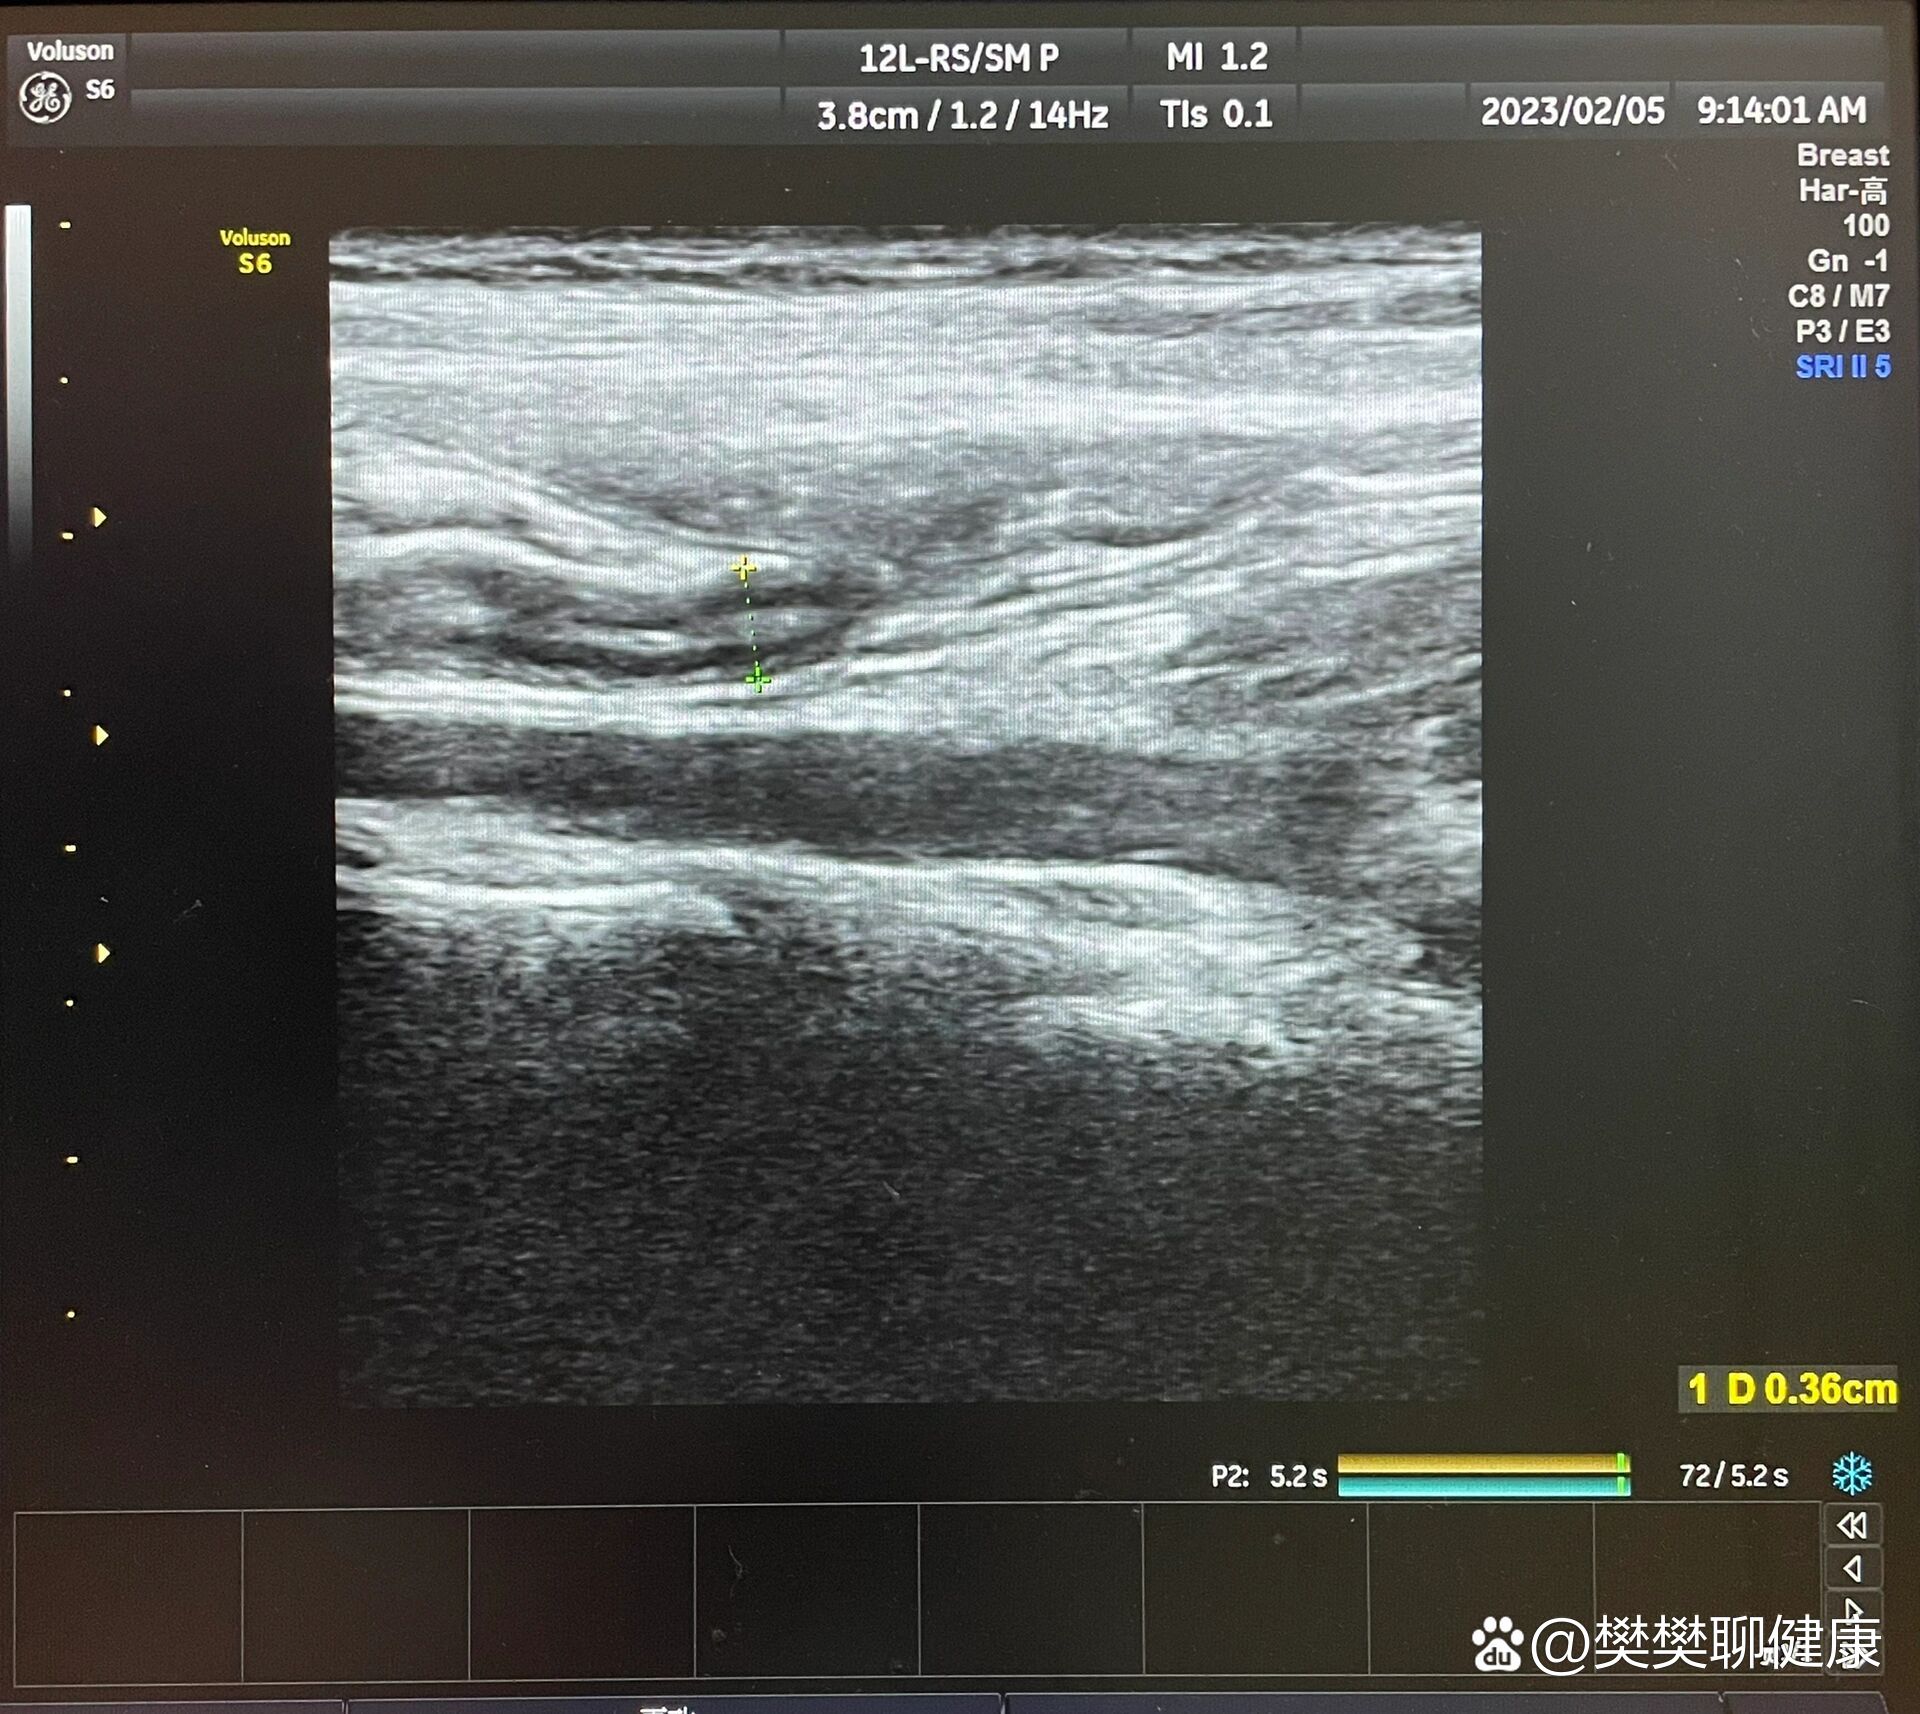

小孩阑尾炎超声诊断的挑战与影像分析

图片尺寸614x709